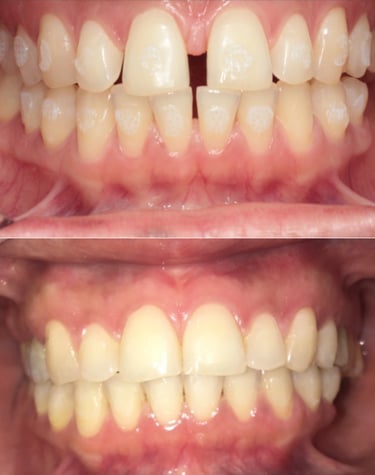

EVOLUÇÃO